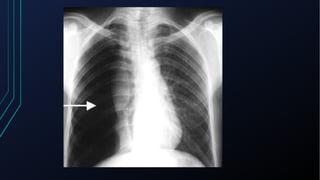

Pneumotórax

• Presença de ar livre no espaço pleural

• Espontâneo

• Primário x Secundário

• Traumático

• Devido a trauma direto ou indireto

• Iatrogênico

• Resultante de procedimento médico

• Geralmente dor súbita, aguda e intensa, podendo estar associada a

dispneia

• Ao exame:

• Redução da expansibilidade do lado acometido

• Redução do frêmito tóraco-vocal

• Percussão timpânica

• Murmúrio vesicular reduzido/ausente